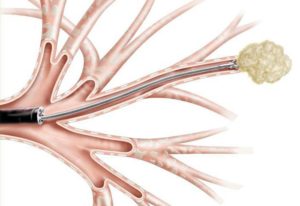

Проводится во время бронхоскопии, которая заключается во введении в дыхательные пути гибкой трубки (бронхоскопа).

Для выполнения биопсии, то есть загрузки фрагмента легочной ткани, врач вводит через бронхоскоп специальные пинцеты, которыми происходит отсечение небольшого участка паренхимы легких.

- При помощи специального прибора – бронхоскопа – проводится трансбронхиальная биопсия легких.

- Процедура назначается при подозрении на поражение легких инфекцией или формирование патологических новообразований рядом с бронхами.

- Чтобы взять немного легочной ткани из легких, которые повредила одна из перечисленных болезней, врач прокалывает стенку бронхов и вводит в полученную дырочку щипцы, забирая 7 фрагментов биологического материала.